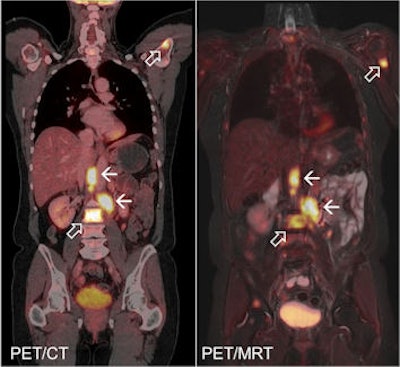

PET/CT (left) and PET/MR (right) images of patient with metastasising carcinoma of the ovaries. Image courtesy of Dr. Karsten Beiderwellen, Essen University Hospital.PET/MRI is technically quite demanding, according to Dr. Karsten Beiderwellen, from the Institute of Diagnostic and Interventional Radiology at Essen. For example, it is necessary to ensure that the strong MRI magnetic fields do not interfere with PET diagnostic procedures. Conversely, the PET components must be designed so that their elements are MRI-compatible. He explained that PET/MRI has advantages over the combination of PET and CT.

"First, MRI gives us a better soft-tissue contrast. This is particularly helpful for smaller tumors in soft tissues like the liver, and also in the brain, because the differentiation from the surroundings is much better," he explained. "With PET/CT, we take the CT and the PET one after the other and then have to put them together. With PET/MRI this is done simultaneously. This is a particular advantage with the pelvis minor, because the bladder fills during the investigation and this displaces the adjacent structures somewhat."

The Essen team is now working on a direct comparison between PET/MRI and PET/CT in patients with ovarian and cervical cancer. Both organs lie within the pelvis minor, and this region is well suited to PET/MRI because many soft-tissue structures there are closely adjacent. Of 12 patients in the study, all were clinically suspected of having a recurrence of their cancer. Over time, it became apparent that only 10 of them did in fact have a recurrence. The patients were first investigated with PET/CT and directly afterward with PET/MRI.

"So far we have managed to identify all tumor recurrences reliably with both methods. However, small lesions of the liver and also some soft-tissue lesions which were not clear were better characterized with PET/MRI," he noted.